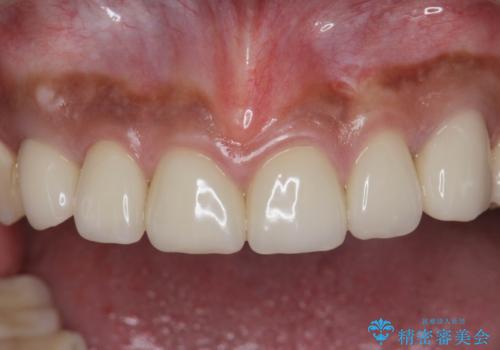

複数箇所コンポジット充填された前歯をセラミック治療

- コンポジットレジンの充填箇所がすり減ってしまい、形の悪くなった前歯の治療を希望され来院されました。

充填部位が大きく、再度充填をするには神経と近くなり抜髄のリスクが高まるため、劣化の少ないセラミックでフルカバーするセラミッククラウン治療を行うこととしました。

- 79.2万円(ジルコニアクラウン×6・仮歯×6)費用は治療当時の料金となります